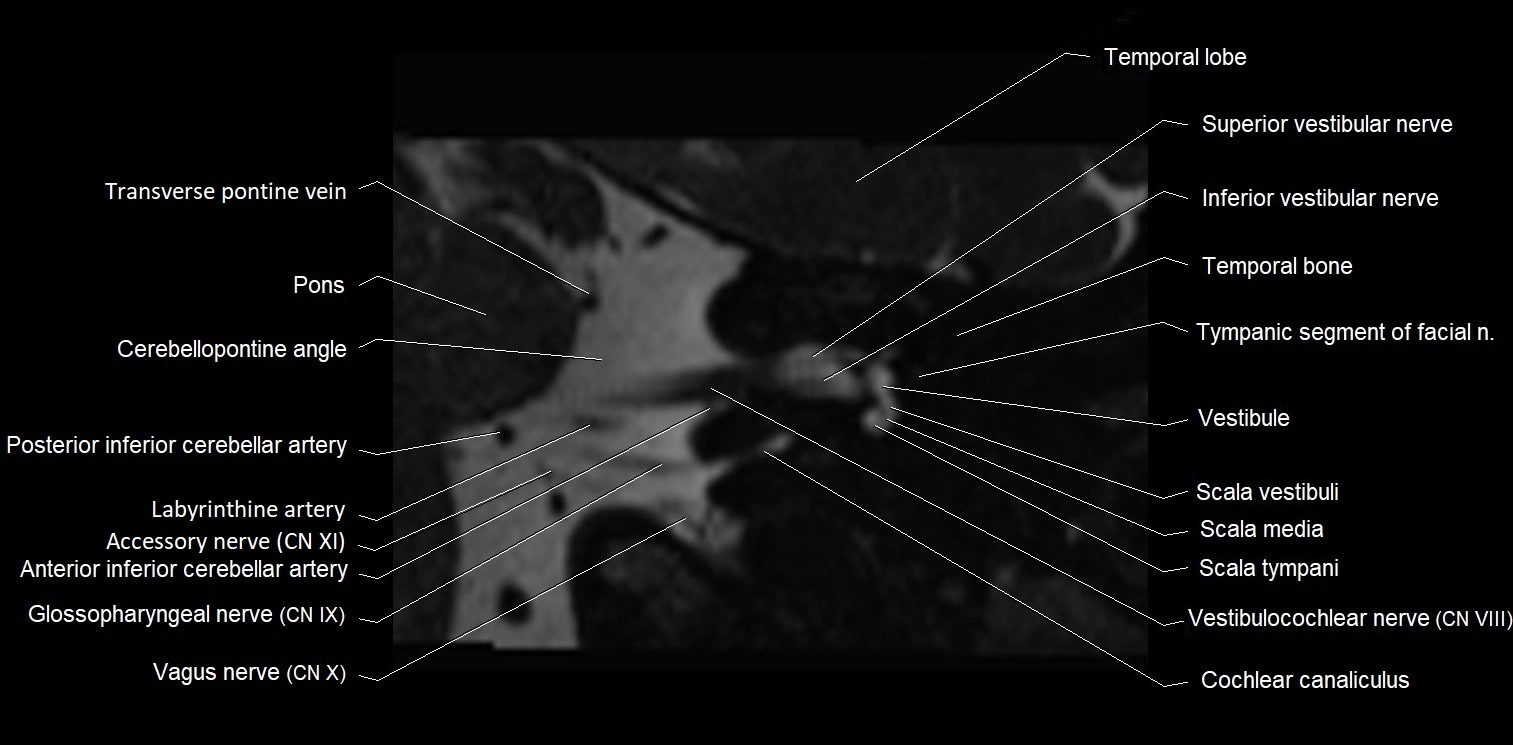

image